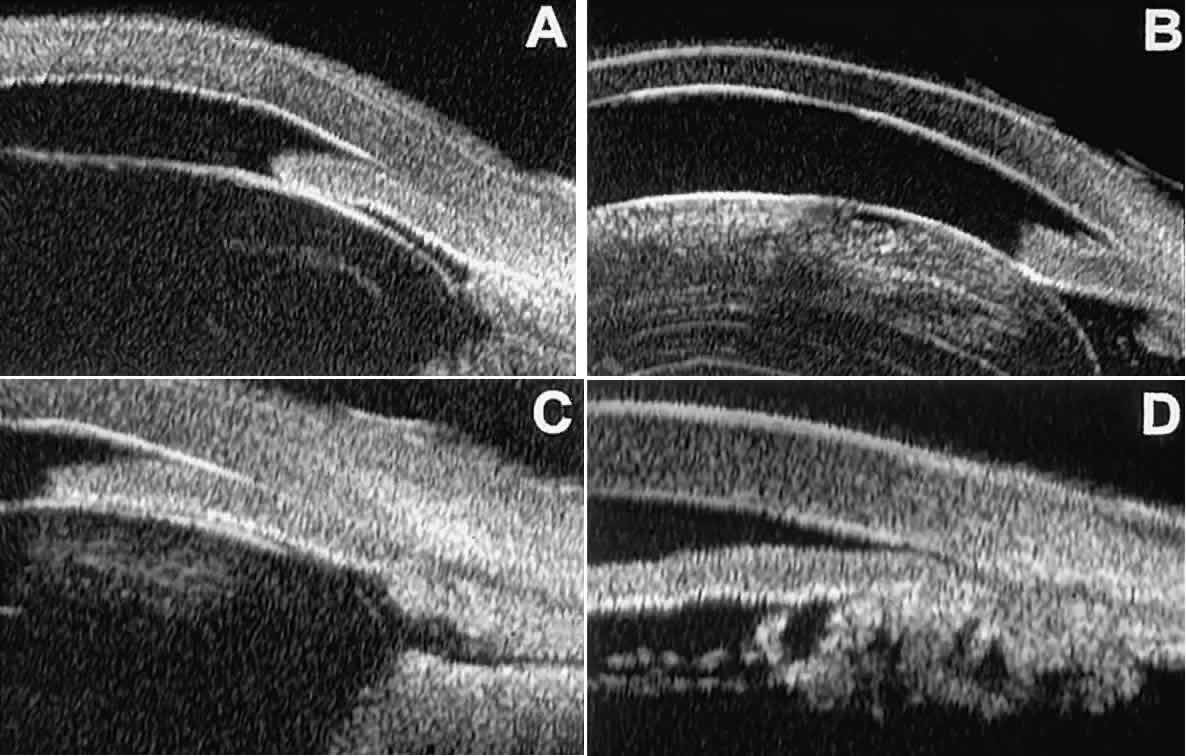

In eyes with a narrow angle, UBM shows the extent of angle closure, reveals the depth of the anterior and posterior chambers, and identifies pathologic processes pushing the lens and iris forward (Fig. 11).2–4,8 UBM has been able to differentiate between primary angle closure (i.e., cases of angle closure without additional pathology responsible for the anterior lens-iris displacement [see Fig. 11A] and secondary angle closure due to processes such as lens swelling and dislocation (see Fig. 11B), massive hemorrhagic retinal detachment pushing the lens and iris anteriorly (see Fig. 11C), and multiple neuroepithelial cysts of the iridociliary sulcus (see Fig. 11D).

Fig. 11. Angle configuration in eyes with angle-closure glaucoma. A. Primary angle-closure glaucoma with anterior displacement of lens and iris. B. Angle closure secondary to swollen, cataractous lens (phakomorphic angle closure). C. Angle closure secondary to massive hemorrhagic retinal detachment; the subretinal blood is evident in the lower right corner of the photograph. D. Angle closure secondary to multiple peripheral iris cysts.

Postoperative UBM imaging of the anatomic changes caused by glaucoma surgery often helps to explain mechanisms of success and failure of the various surgical procedures (Fig. 12).3,4 After laser iridotomy, UBM can show whether the iridotomy is partial thickness (see Fig. 12A) or full thickness (see Fig. 12B) and whether the plane of curvature of the peripheral iris has changed compared with the pretreatment findings. After trabeculectomy (see Fig. 12C), UBM can show whether the scleral aperture is patent or blocked internally, whether the peripheral iridectomy is open or blocked, and whether the filtering bleb is flat, shallow, or deep.9 After tube shunt surgery (see Fig. 12D), UBM can show the position of the tip of the tube and whether its orifice is open or plugged.

Fig. 12. UBM features in glaucomatous eyes after treatment or filtering surgery. A. Incomplete peripheral iridectomy created by laser. B. Full-thickness peripheral iridectomy created by laser. C. Postoperative features of trabeculectomy including peripheral iridectomy, inner scleral defect, thin residual scleral flap, and overlying conjunctival filtering bleb. D. Tube shunt projecting radially into anterior chamber; note that the tube “shadows” deeper structures.